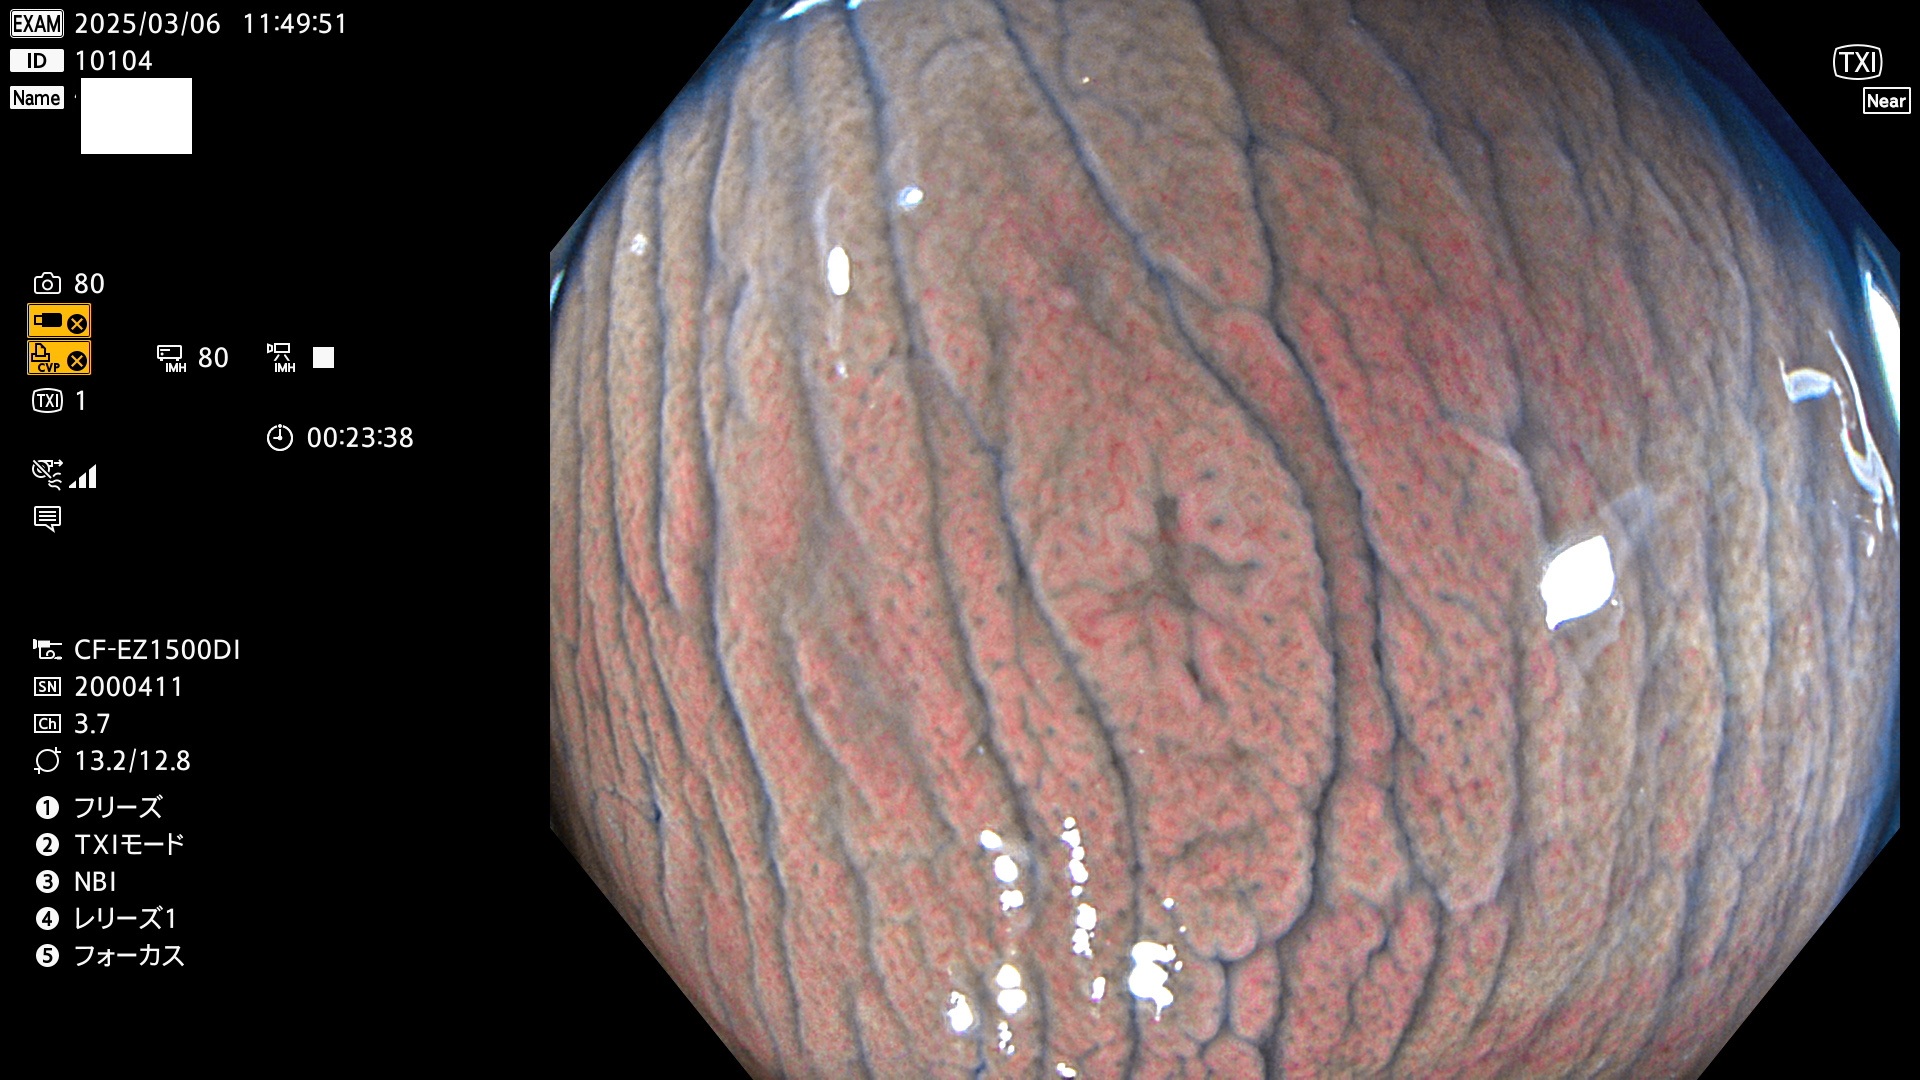

今週のUb、Uc型腺腫

完全に平坦な物をUb、陥凹している物をUcと呼びます。最も発見が難しく危険な病変です。

毎週の検査(木・金・土・日)に発見されたUb、Uc型・腺腫を、その週の日曜の夜にUPし1週間、提示します。

抽出の対象期間 2025年3月6日〜3月9日の4日間(48件の検査)5個 (5/48=10%)